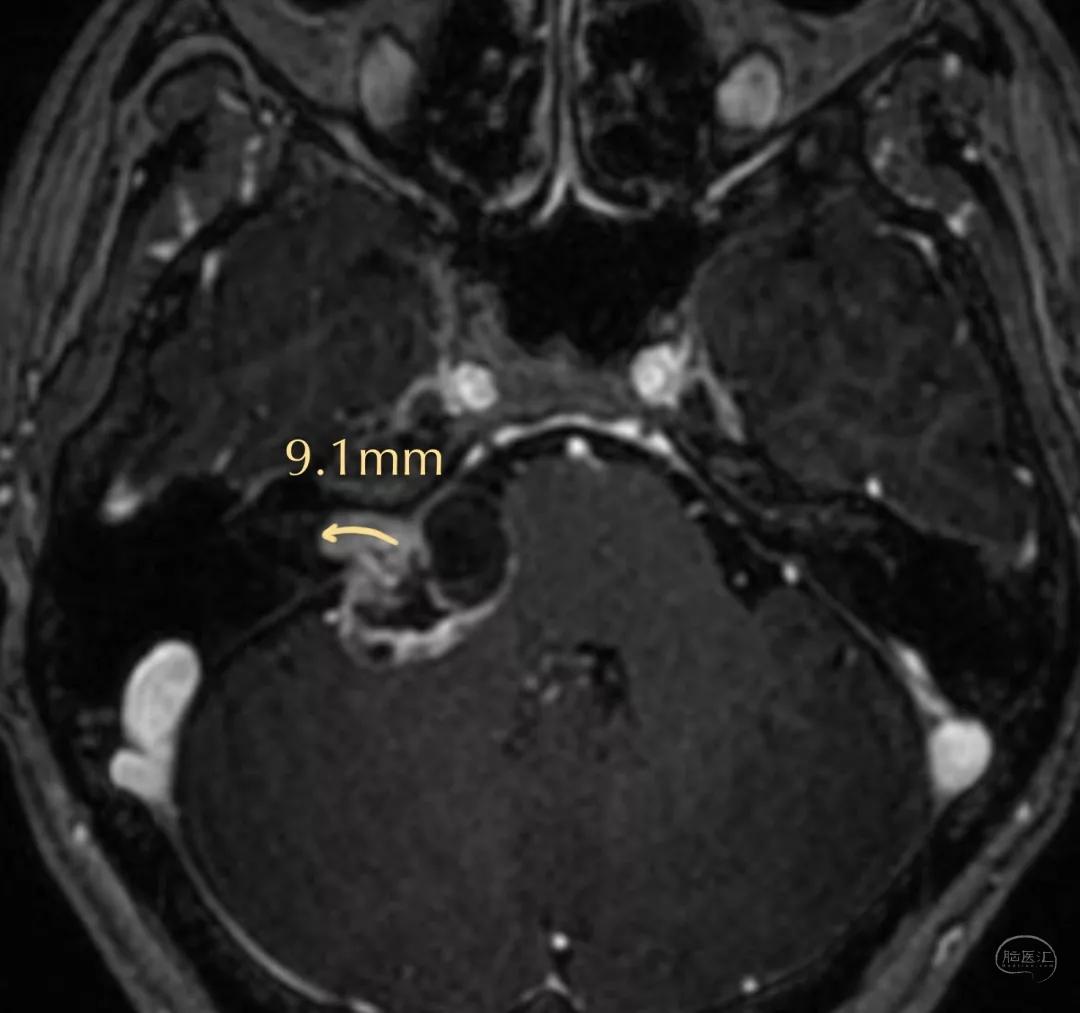

术前影像

术前影像资料

(肿瘤长入内听道内较深-9.1mm)

术前内听道扩大(右侧)